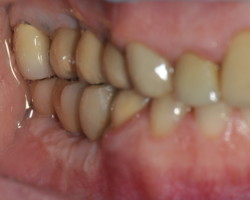

Avant-Après :